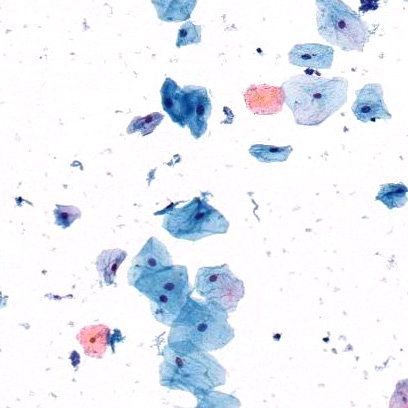

Aerospray Cytology can stain many sample types

See What You Need to See

AEROSPRAY® TECHNOLOGY GIVES

SUPERIOR STAINING RESULTS

• Superior staining results in 3-15 minutes with an easy-to-use process

• Consistent, reliable, and standardized staining results across multiple labs

• Reduced cross-contamination with a fresh application of stain applied to every slide

• Minimized stain waste with an 18-month reagent shelf-life